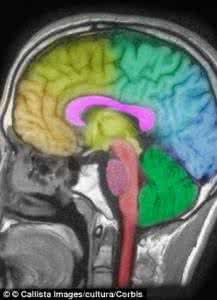

据国外媒体1月2日报道,你是不是有过这样的感觉:一晚上没睡好,第二天起来就觉得头好像被什么东西打了一样。科学家说,这不是危言耸听。一项发表于《Sleep》的新研究显示,只要一晚上不睡觉,你的大脑就会发生变化,影响和头部遭到重物打击一样。

睡眠是高等脊椎动物周期性出现的一种自发的和可逆的静息状态,表现为机体对外界刺激的反应性降低和意识的暂时中断。人的一生大约有1/3的时间是在睡眠中度过的。当人们处于睡眠状态中时,可以使人们的大脑和身体得到休息、休整和恢复,适量的睡眠有助于人们日常的工作和学习。科学提高睡眠质量,是人们正常工作学习生活的保障。

睡眠是一种主动过程,睡眠是恢复精力所必需的休息,有专门的中枢管理睡眠与觉醒,睡时人脑只是换了一个工作方式,使能量得到贮存,有利于精神和体力的恢复;而适当的睡眠是最好的休息,既是维护健康和体力的基础,也是取得高度生产能力的保证。接受处理内外刺激并做出反应的兴奋度较高的神经细胞因防止没有经过深加工的刺激联结相互干扰,这就表现为缓解疲劳。而睡眠质量不高是指屏蔽度不够或睡眠时间不足以充分消化刺激联结的现象。嗜睡则是病态的过多过久屏蔽。这些都是神经控制不足的表现。在睡眠中由于主动性活动减弱,身体的状态也得到恢复。